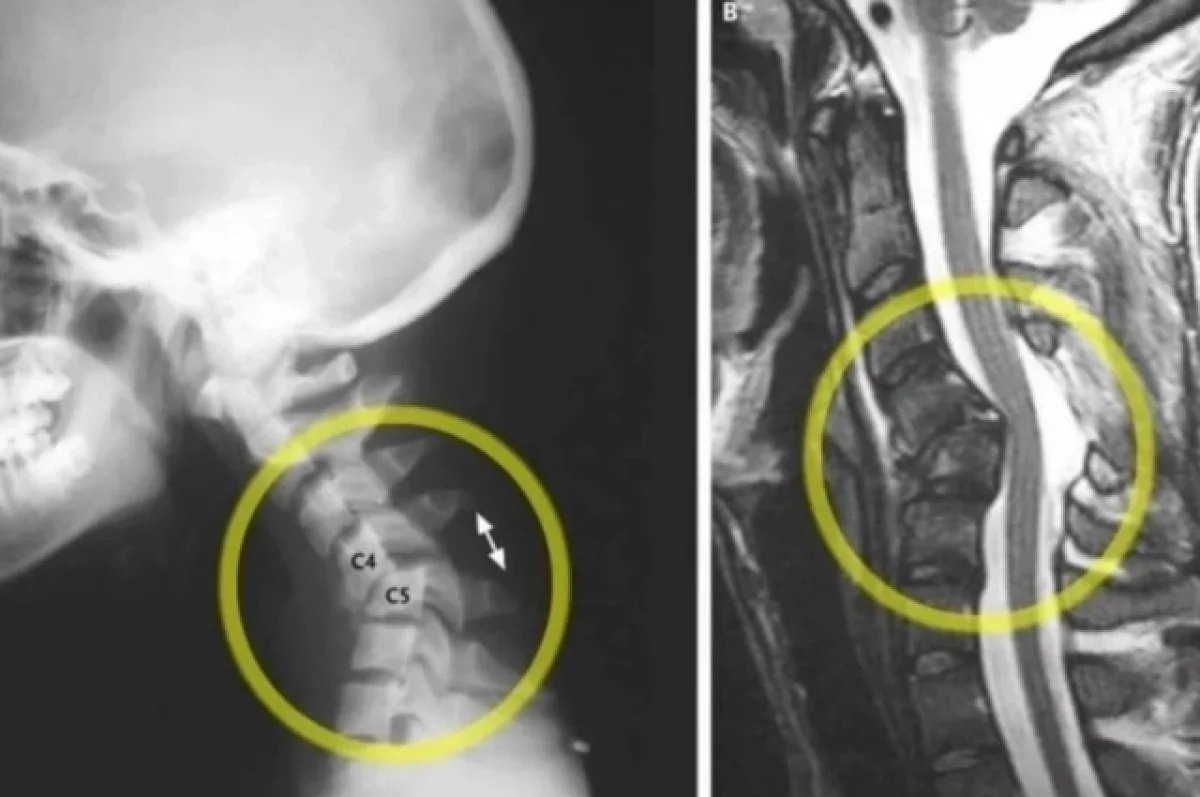

Особую подвижность и слабость имеет шейный отдел позвоночника. При значительных травмах возможен перелом шейных позвонков и повреждение спинного мозга, что влечет за собой немедленную гибель.